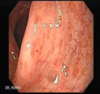

Quais são os possíveis achados endoscópicos na Retocolite Ulcerativa Idiopática?

- Acomete preferencialmente o reto e o cólon descendente

- Mucosa hiperemiada e friável ao toque, com pseudopólipos

- Acometimento contínuo

- Inicia-se no reto e não acomete o íleo

- Acometimento mucoso exclusivo

- Resultado da biópsia: Abscessos de criptas intestinais